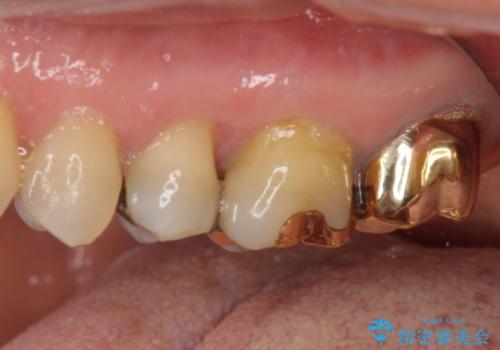

外れてしまった銀歯 セラミックインレーで自然な仕上がりに

- 奥歯の銀歯が外れてしまったため、セラミック治療を希望された患者様です。

セラミックインレーによる修復治療を実施しました。

正面から見える場所であったため、セラミックインレーで自然な口元にすることができました。